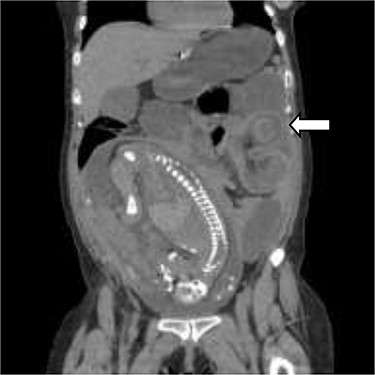

Coronal view of the CT scan showing intussusception (white arrow—sausage-shaped thickened bowel Wall).